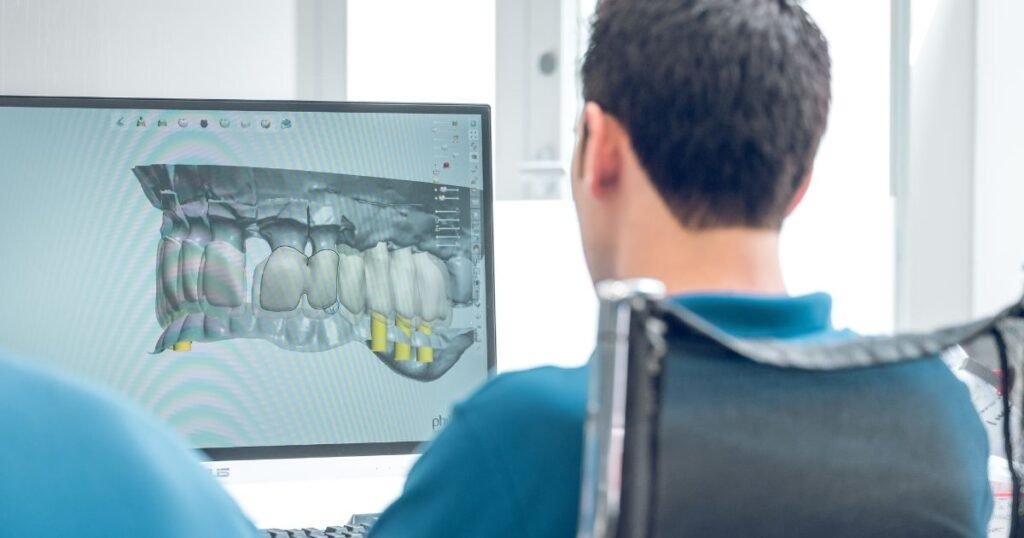

En AR Odontología Digital trabajamos con planificación digital e impresión 3D para diseñar sonrisas personalizadas: más armónicas, luminosas y equilibradas, sin perder tu esencia.

Ya no se trabaja solo con pruebas en boca, sino con herramientas digitales que permiten prever cómo quedará tu sonrisa.

En una primera consulta tomamos fotografías, registros y, cuando es necesario, escaneos 3D.

Con esa información, diseñamos sobre pantalla distintas opciones de forma y tamaño de dientes, siempre teniendo en cuenta:

De este modo, podés ver una simulación previa y dar tu opinión.

Utilizamos sistemas CAD/CAM e impresión 3D para confeccionar las carillas de porcelana pura con el espesor y la forma exactos que se planificaron.